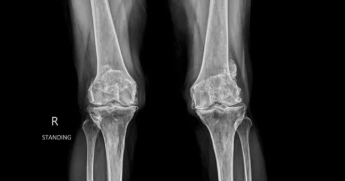

| 초기 (1~2기) | 통증 가볍고 간헐적, 관절 사이 간격 감소 시작 |

| 중기 (3기) | 연골 마모 심해짐, 관절음, 변형 시작, 일상생활 불편 |

| 말기 (4기) | 연골 거의 소실, 뼈끼리 마찰, 인공관절 수술 고려 |

→ X-ray, MRI, 관절 초음파 등으로 진단 가능